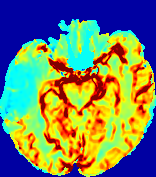

4.3.2 Diffusion Imaging via Advection-Diffusion

Slice #1Slice #2Slice #3Slice #4Slice #5Slice #6Dgtsuperscript𝐷gtD^{\text{gt}}Refer to captionRefer to captionRefer to captionRefer to captionRefer to captionRefer to captionDestsuperscript𝐷estD^{\text{est}}Refer to captionRefer to captionRefer to captionRefer to captionRefer to captionRefer to captionRefer to caption0.300.300.300.240.240.240.180.180.180.120.120.120.060.060.060.000.000.00(mm2/s)𝑚superscript𝑚2𝑠(mm^{2}/s)𝐕est𝟐subscriptnormsuperscript𝐕est2\|\bf{V}^{\text{est}}\|_{2}Refer to captionRefer to captionRefer to captionRefer to captionRefer to captionRefer to captionRefer to caption0.00300.00300.00300.00240.00240.00240.00180.00180.00180.00120.00120.00120.00060.00060.00060.00000.00000.0000(mm/s)𝑚𝑚𝑠(mm/s)

Figure 15: PIANO identifiability testing: diffusion imaging via advection-diffusion. Top row shows Dgtsuperscript𝐷gtD^{\text{gt}} used for simulating ground truth pure diffusion. Rows below show the estimated Destsuperscript𝐷estD^{\text{est}} and 𝐕est2subscriptnormsuperscript𝐕est2\|{\bf{V}}^{\text{est}}\|_{2} on corresponding slices. Note that the plotted value scale for 𝐕est2subscriptnormsuperscript𝐕est2\|{\bf{V}}^{\text{est}}\|_{2} is 0.01 of that for Dgtsuperscript𝐷gtD^{\text{gt}} and Destsuperscript𝐷estD^{\text{est}}.

Similarly, we test the behavior of PIANO when estimating both advection and diffusion from a pure diffusion-driven process. The goal is to determine if PIANO is able to recognize that there is only diffusion governing the given concentration time-series. We use the same ‘Diffusion Imaging’ data simulation of Sec. 4.2.1 as the concentration dataset, PIANO estimates both velocity 𝐕estsuperscript𝐕est{\bf{V}}^{\text{est}} and diffusivity Destsuperscript𝐷estD^{\text{est}}. Estimation results in Fig. 15 confirm PIANO’s identifiability again: the estimated 𝐕est2subscriptnormsuperscript𝐕est2\|{\bf{V}}^{\text{est}}\|_{2} is almost invisible compared to Destsuperscript𝐷estD^{\text{est}}, even plotted with a 1%percent11\% value range compared to that for Destsuperscript𝐷estD^{\text{est}}. On the other hand, Destsuperscript𝐷estD^{\text{est}} achieves comparable estimation performance as ‘Diffusion Imaging via Diffusion’ in which PIANO predicts Destsuperscript𝐷estD^{\text{est}} alone (shown in Fig. 13).